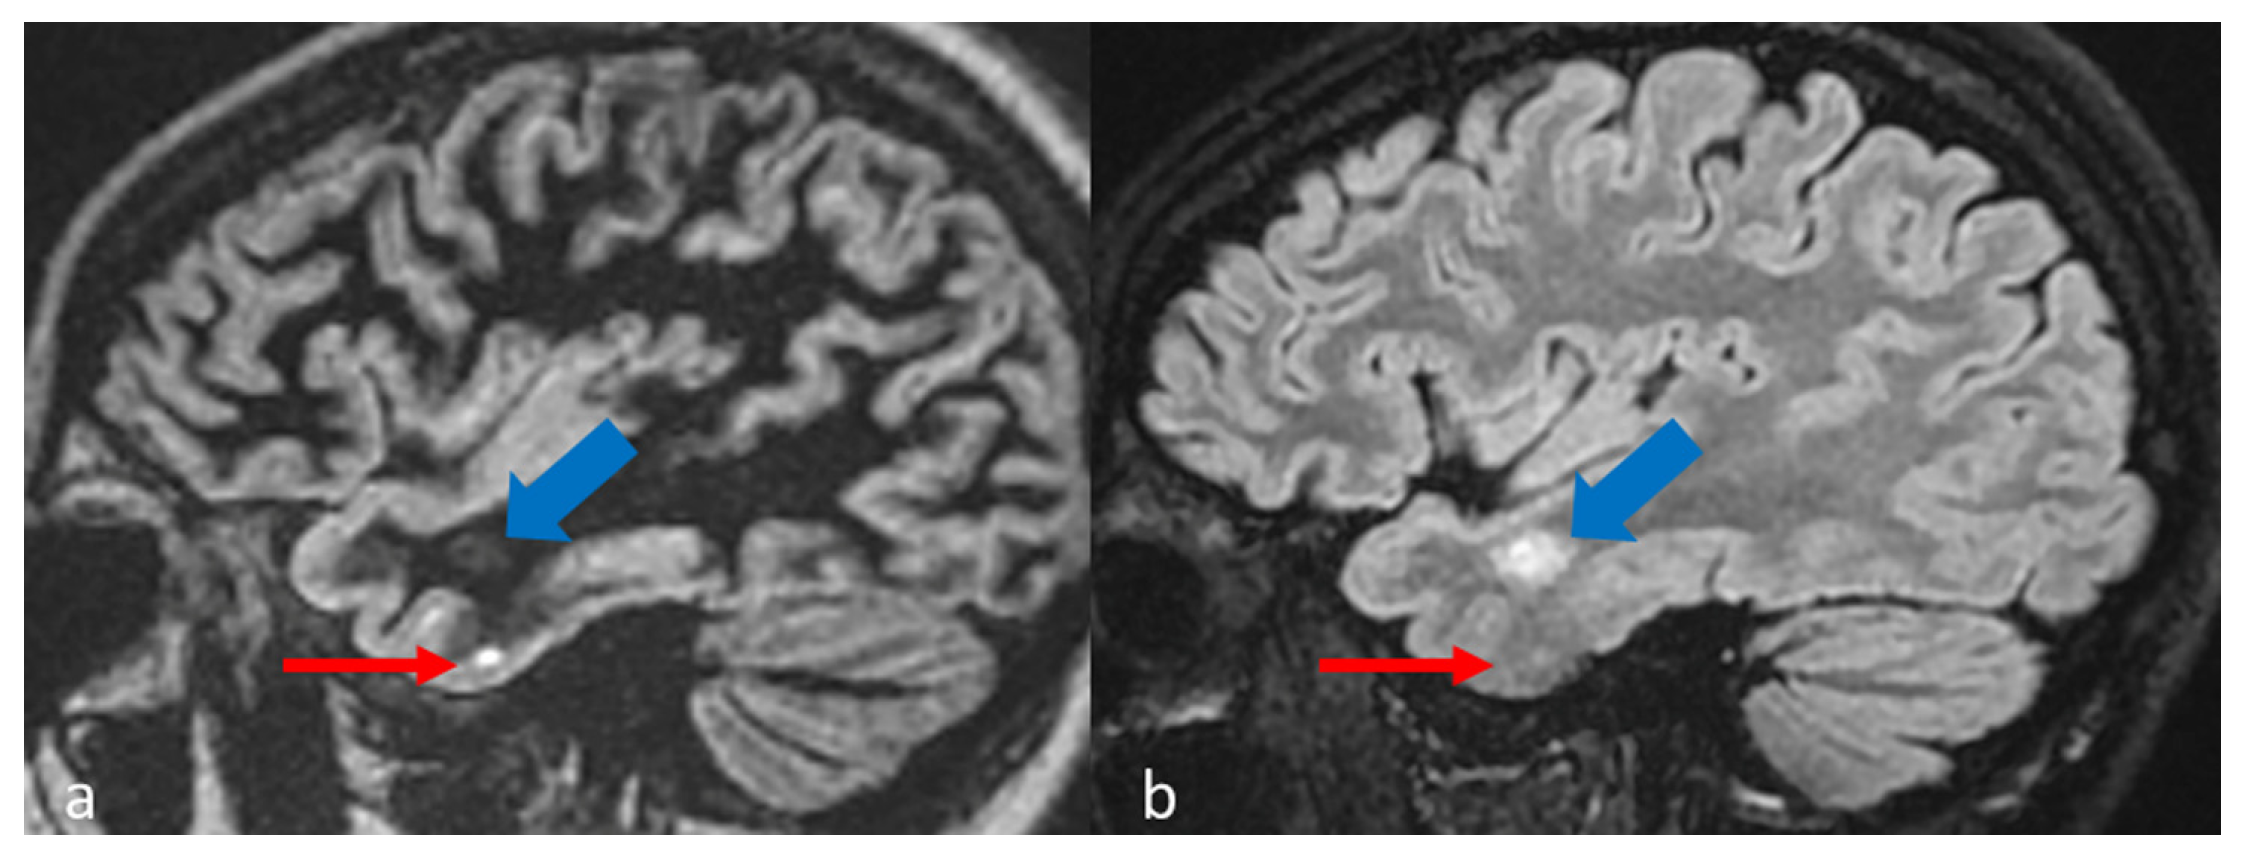

| Practical Recommendation |

| In MS protocol, attention has to be paid to perform DIR before contrast-administration, as post-contrast DIR may suppress active subcortical lesions. |